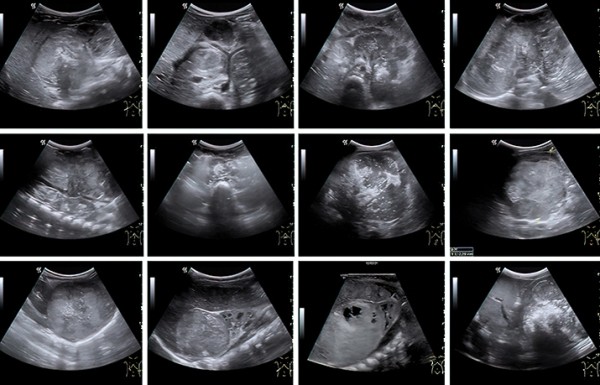

К сожалению, у значительной части пациентов на момент постановки диагноза болезнь уже в распространенной форме. Чаще всего опухоль распространяется в лимфатические узлы, печень, кости и костный мозг (см. рис. 1).

Во время УЗИ на амбулаторном этапе забрюшинная опухоль, как правило, определяется по достижении так называемого диагностического объема в несколько кубических сантиметров. При этом врач уверенно может установить факт наличия образования, его эхоструктуру, чего уже достаточно для направления ребенка на дообследование (см. рис 2).

Рисунок 2. Сонографические варианты нейробластомы.